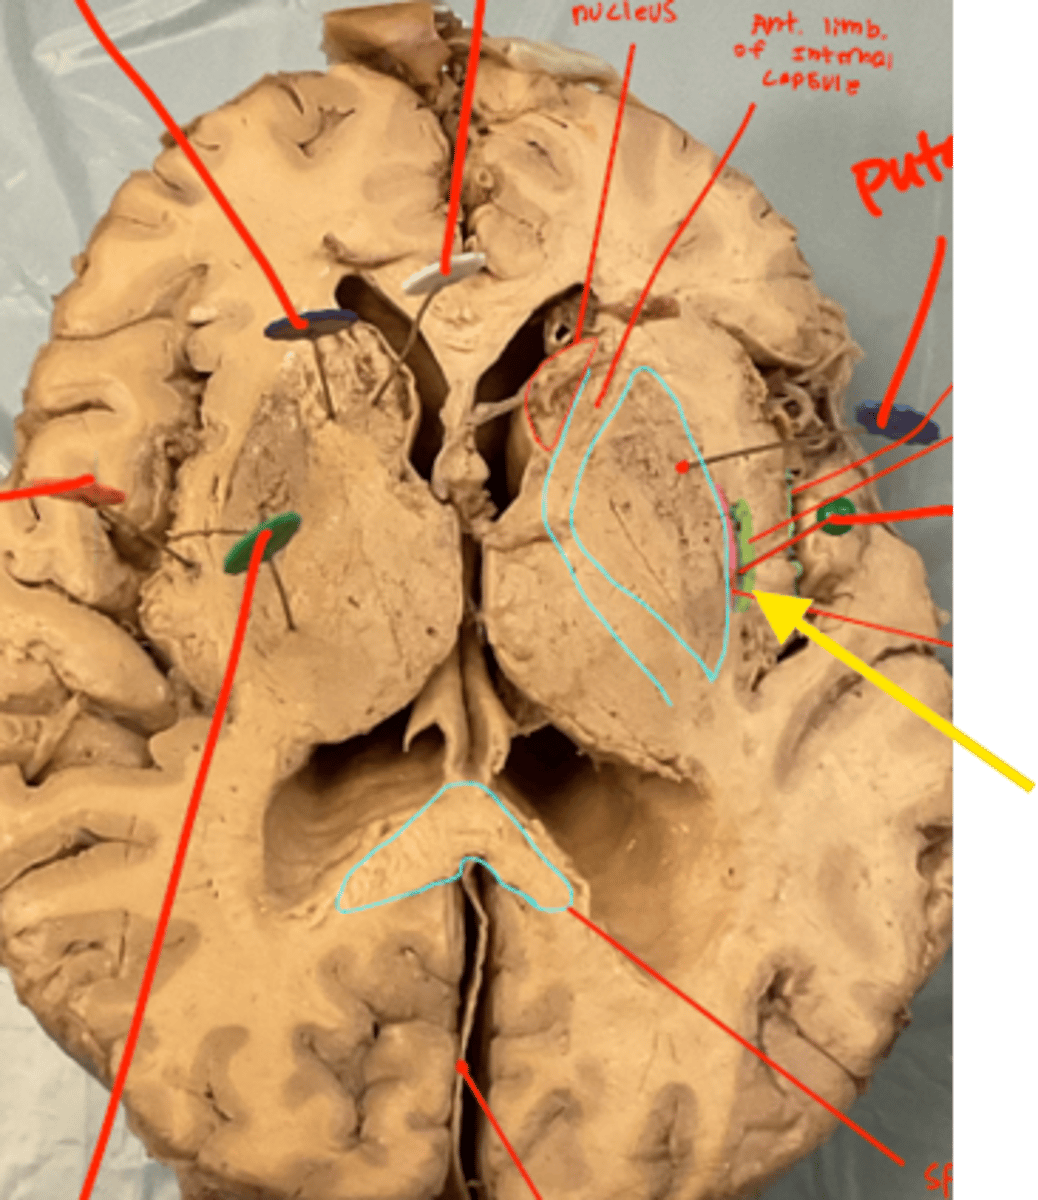

What space is the yellow arrow pointing to?

what space is the yellow arrows pointing to?

what structure is the blue pin in?